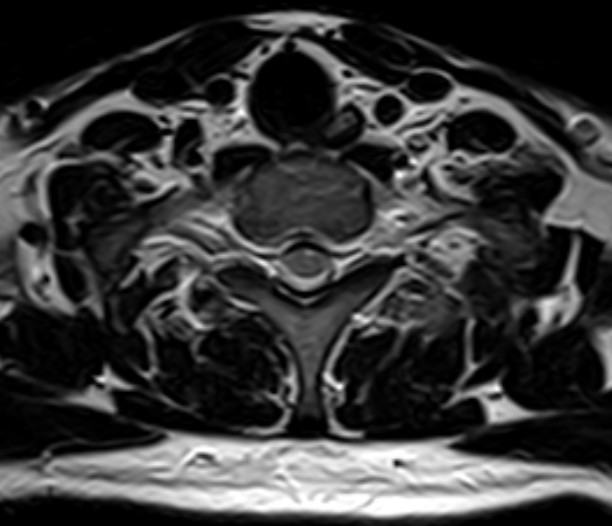

颈椎-T2

1524110739454333.jpg